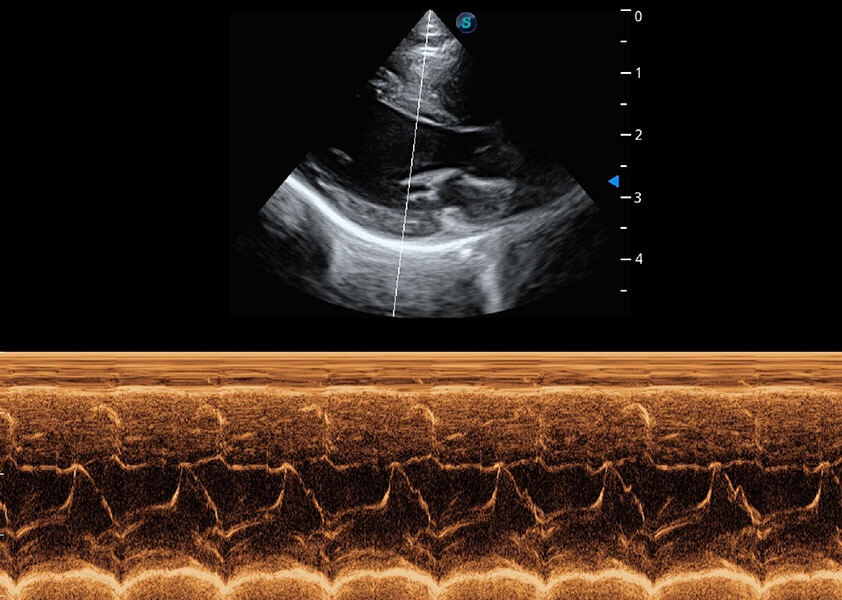

心脏解决方案

ProPet 60 配备了丰富的心脏探头群、先进的成像技术和专业的心脏测量工具,可帮助动物医生为不同体型和生理结构的动物提供心脏和心肌功能的全面评估。

• TDI 组织多普勒成像

实时用颜色表示心肌组织运动,观察和定量组织的运动情况,对快速检测与评估心肌的灌注和活性、电传导及心肌收缩和舒张功能等均能提供重要的诊断信息。

• MQA 心肌定量分析

通过心肌识别技术与二维斑点追踪技术相结合,对心脏的超声图像进行量化分析。计算心肌17个节段的应变、应变率、速度、位移等,并通过牛眼图的形式进行呈现。

• AMM 解剖M型

通过360度任意调节3条M型取样线,在同一心动周期上观察心脏不同位置的运动曲线,得到准确的心功能测量数据,有效评估心肌运动及左心室功能。

• Stress Echo 负荷超声心动图

具备多种协议可选,同时支持17阶段划分法和专业的SE报告。

优异的基础图像

(犬)心脏组织多普勒

(犬)乳头肌短轴

(猫)二尖瓣M型